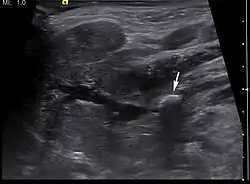

Diagnosis is usually made by characteristic history and physical examination. Diagnosis can be confirmed by x-ray (80% of salivary gland calculi are visible on x-ray), by sialogram, or by ultrasound.

Ultrasound image of sialolithiasis- Stone resulting in inflammation and dilation of the duct[9]